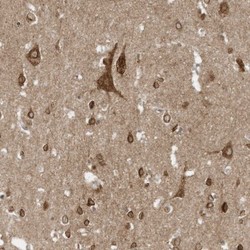

Immunohistochemistry

NBP1-89020 IHC

Method: